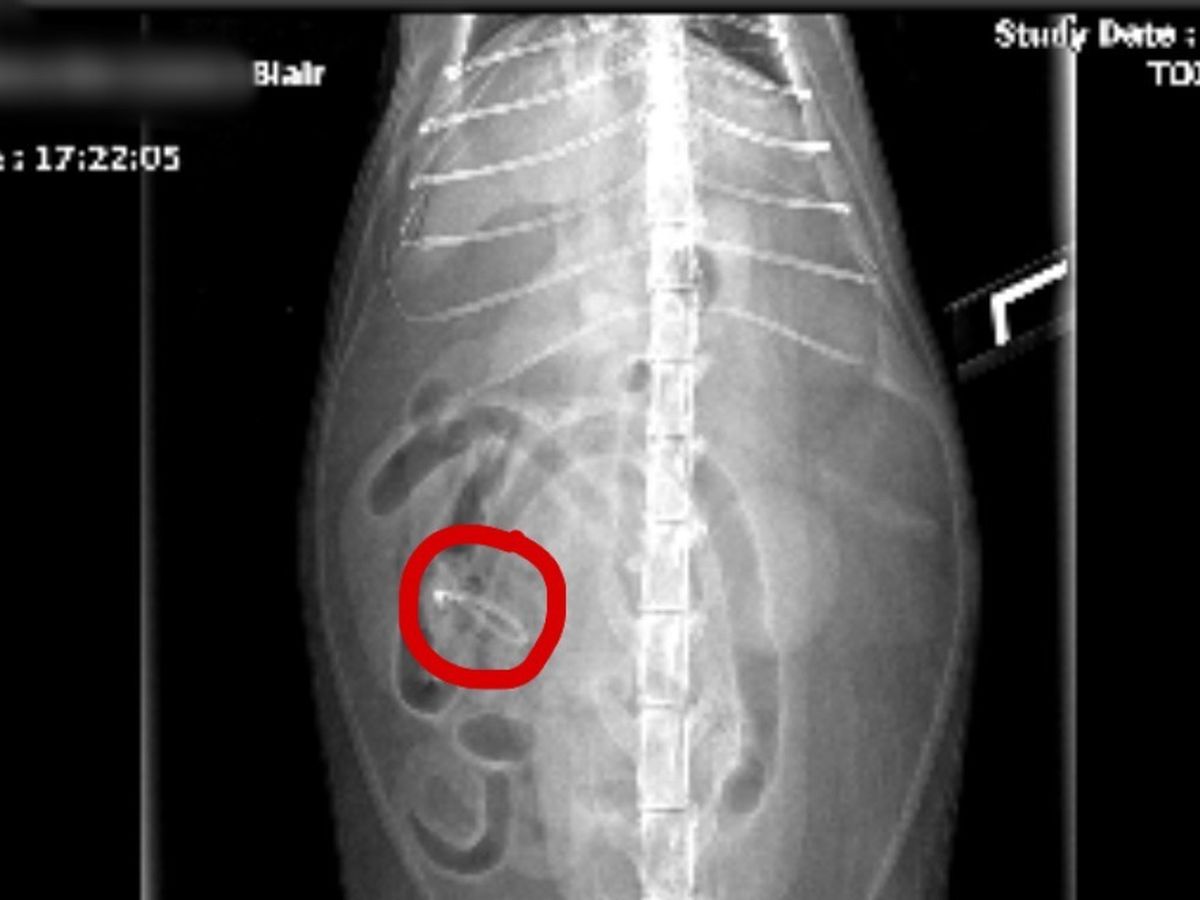

Hi, my name is Cinthya. I am fundraising for my cat Blair who is in need of surgery. Blair has eaten a piece of her toy which is causing her to throw up for the whole day. The Vet have told me the best option for Blair is surgery before it becomes worse. She is very lethargic and won’t eat or drink. I am truly saddened to see how weak my baby is getting by every minute of the day. I am currently not financially able to help pay for Blair’s surgery. I will genuinely appreciate every bit of money donated to help my loving Blair go back to being herself.